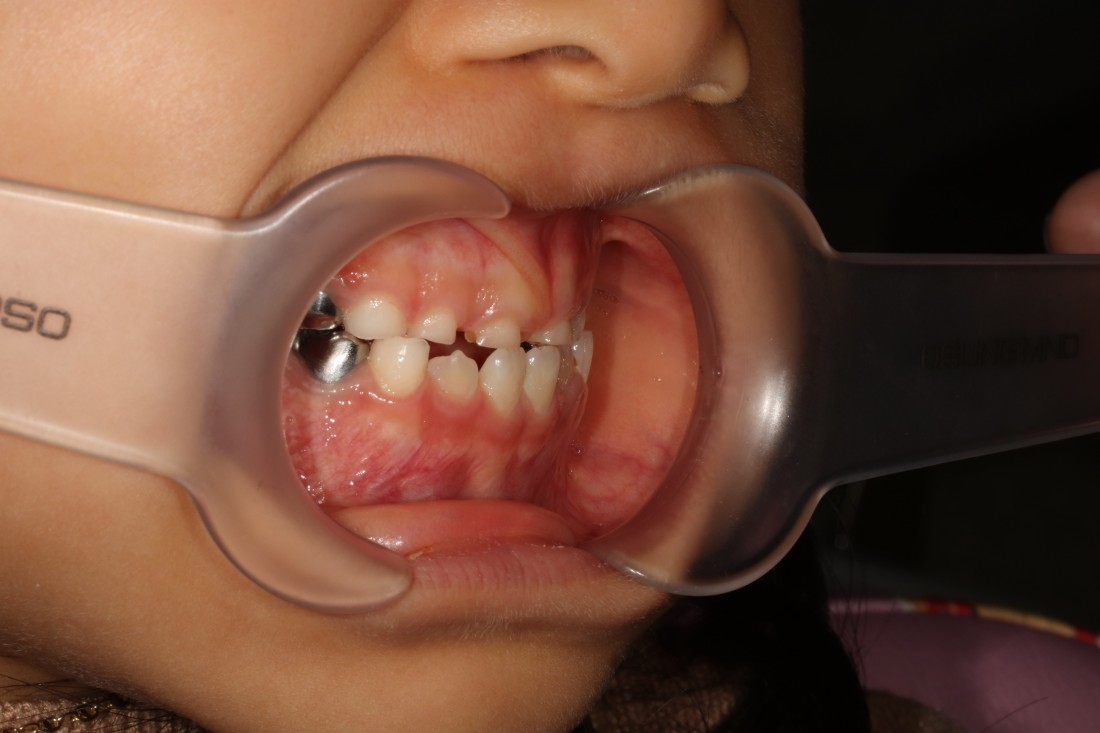

광주 부정교합 치과에서는

프리올소 교정장치를 이용하여

반대교합을 개선하고 있습니다.

프리올소 교정장치는

일본의 교정전문의가 개발한

뺐다 꼈다 할 수 있는

탈착식 교정장치를 말하는데요.